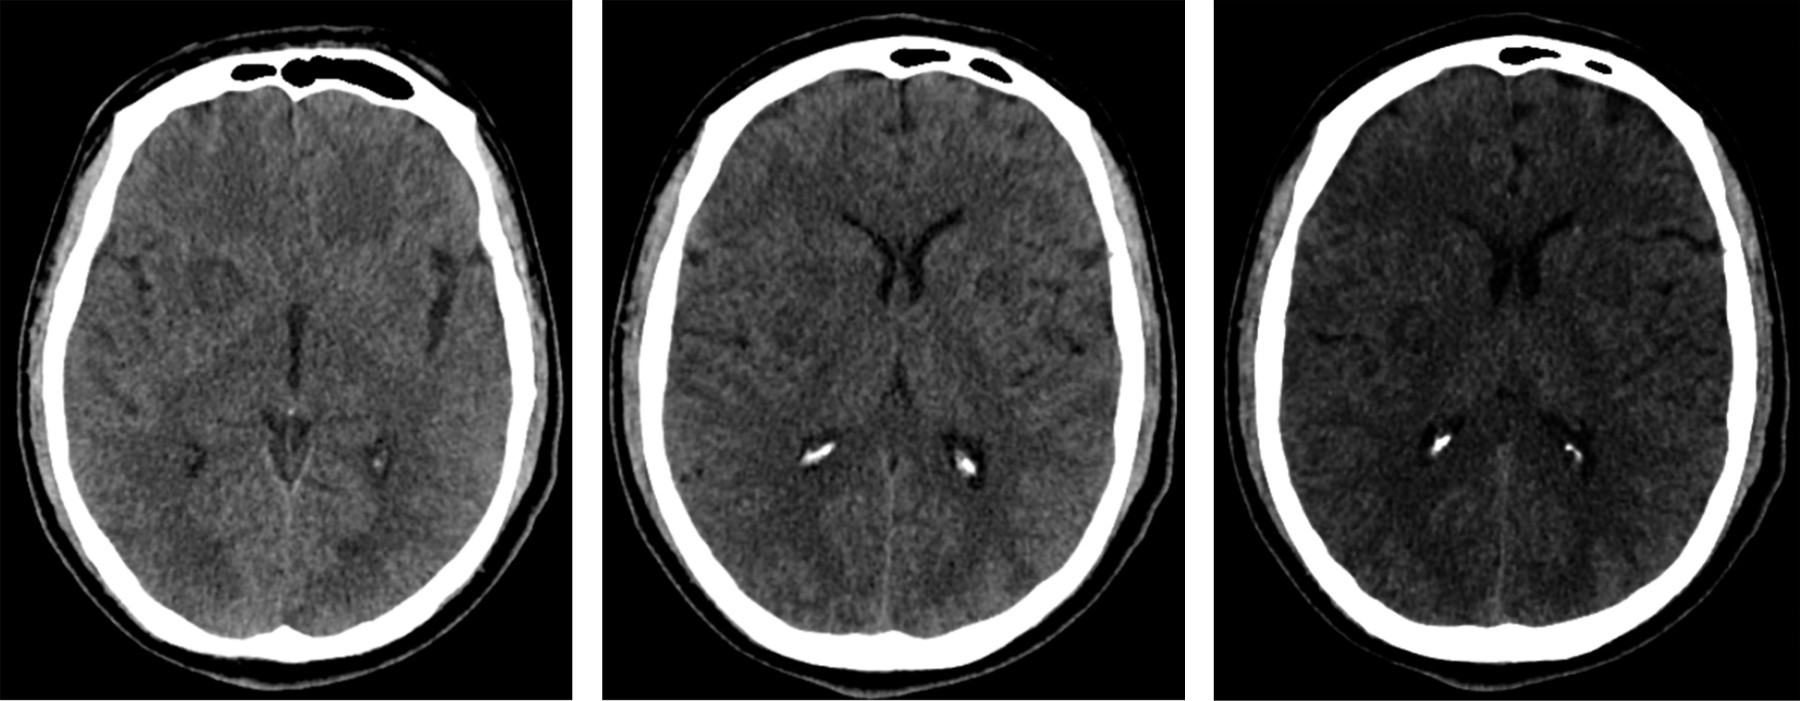

Hombre de 46 años de edad, diestro, que tiene como profesión técnico en estructuras de aeronaves, que ingresa por cefalea de cinco días, holocraneana, de inicio progresivo, tipo punzada, alcanza máxima intensidad 8/10, sin foto ni fonofobia, sin nauseas ni emesis, que aumenta con cambios de posición y maniobras de Valsalva, que cede temporalmente con acetaminofén y diclofenaco, permite conciliar sueño, en algunas ocasiones la cefalea despierta, sin antecedentes de importancia para la enfermedad actual; al examen físico y neurológico dentro de límites normales, se toman estudios de neuroimagen como parte de la atención integral, los resultados de la tomografía craneal se muestran en la Figura 1.

Figura 1